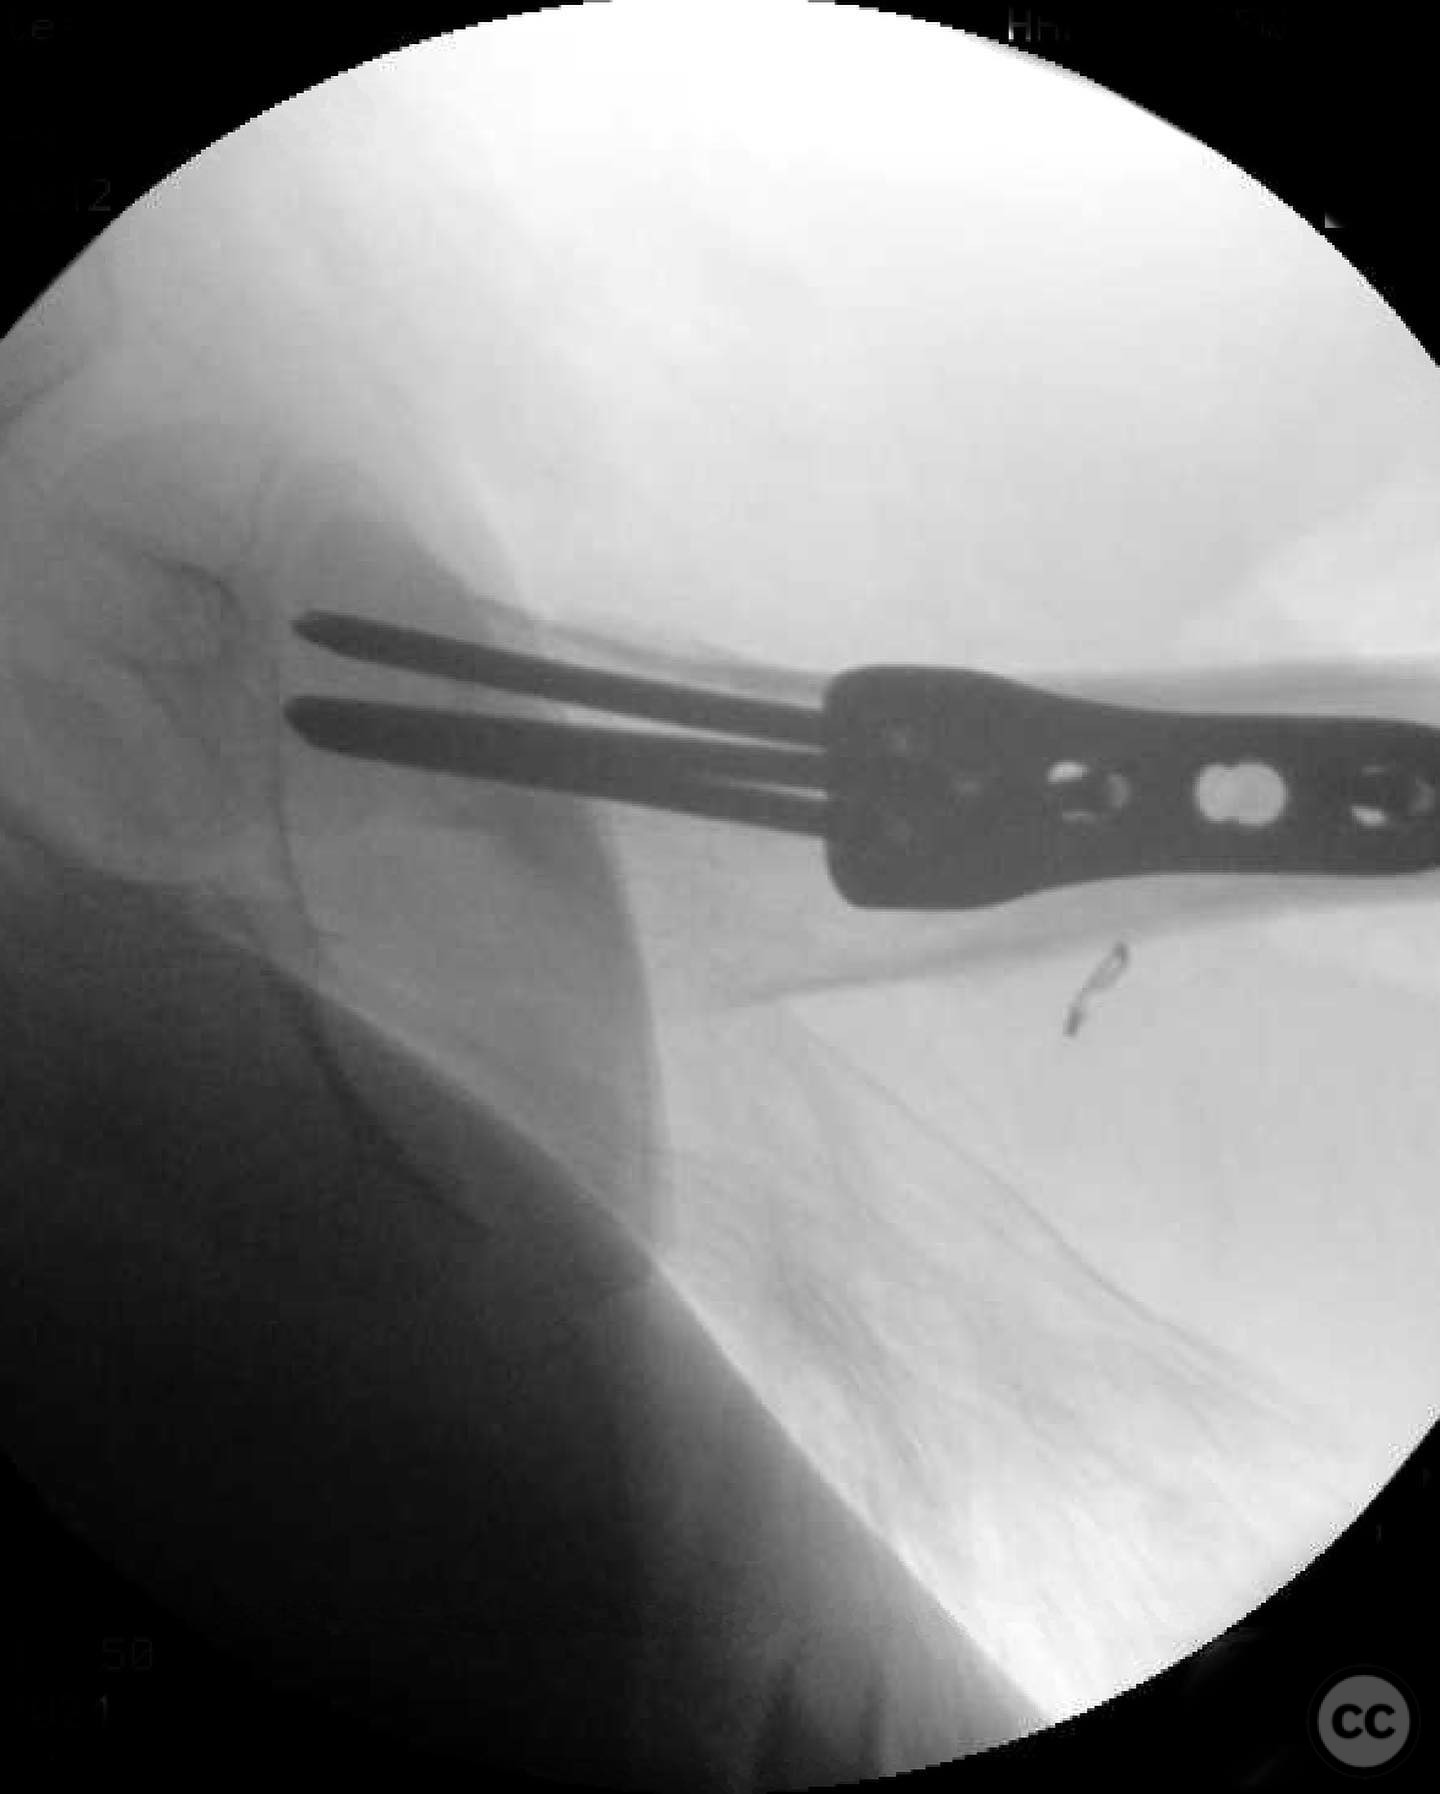

Anatomical surgical approach:  A modified Smith-Petersen approach was utilized, involving an incision along the anterior aspect of the hip, allowing for direct visualization of the femoral neck. Subperiosteal dissection was performed to expose the fracture site without compromising the surrounding musculature. A separate lateral approach was employed for the application of fixation devices.

Operative remarks:

The surgeon emphasized the importance of achieving a high-quality reduction and stable fixation due to the displacement pattern of the fracture. A meticulous surgical approach was critical to avoid malreduction, which is not well-tolerated in pediatric patients. The modified Smith-Petersen approach provided excellent visualization for anatomic reduction, minimizing soft tissue damage.

Orthopaedic implants used:   Angle stable static device (specific brand not mentioned).